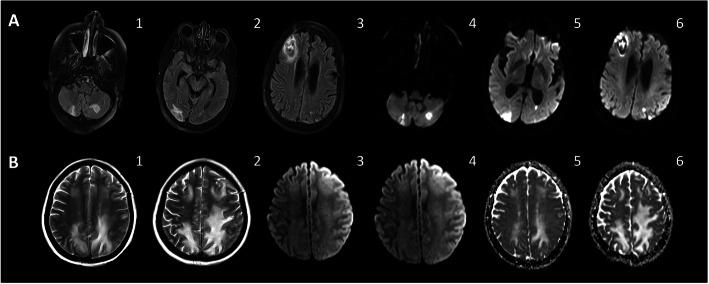

Coronavirus disease 2019 (COVID-19) is a highly infectious pandemic caused by a novel coronavirus called severe acute respiratory syndrome coronavirus 2 (SARS-CoV-2). It frequently presents with unremitting fever, hypoxemic respiratory failure, and systemic complications (e.g., gastrointestinal, renal, cardiac, and hepatic involvement), encephalopathy, and thrombotic events. The respiratory symptoms are similar to those accompanying other genetically related beta-coronaviruses (CoVs) such as severe acute respiratory syndrome CoV (SARS-CoV) and Middle East Respiratory Syndrome CoV (MERS-CoV). Hypoxemic respiratory symptoms can rapidly progress to Acute Respiratory Distress Syndrome (ARDS) and secondary hemophagocytic lymphohistiocytosis, leading to multi-organ system dysfunction syndrome. Severe cases are typically associated with aberrant and excessive inflammatory responses. These include significant systemic upregulation of cytokines, chemokines, and pro-inflammatory mediators, associated with increased acute-phase proteins (APPs) production such as hyperferritinemia and elevated C-reactive protein (CRP), as well as lymphocytopenia. The neurological complications of SARS-CoV-2 infection are high among those with severe and critical illnesses. This review highlights the central nervous system (CNS) complications associated with COVID-19 attributed to primary CNS involvement due to rare direct neuroinvasion and more commonly secondary CNS sequelae due to exuberant systemic innate-mediated hyper-inflammation. It also provides a theoretical integration of clinical and experimental data to elucidate the pathogenesis of these disorders. Specifically, how systemic hyper-inflammation provoked by maladaptive innate immunity may impair neurovascular endothelial function, disrupt BBB, activate CNS innate immune signaling pathways, and induce para-infectious autoimmunity, potentially contributing to the CNS complications associated with SARS-CoV-2 infection. Direct viral infection of the brain parenchyma causing encephalitis, possibly with concurrent neurovascular endotheliitis and CNS renin angiotensin system (RAS) dysregulation, is also reviewed.